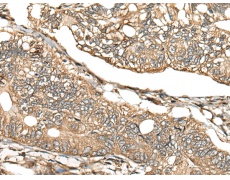

IHC positive control: |

Human gastric cancer |

ELISA, IHC |